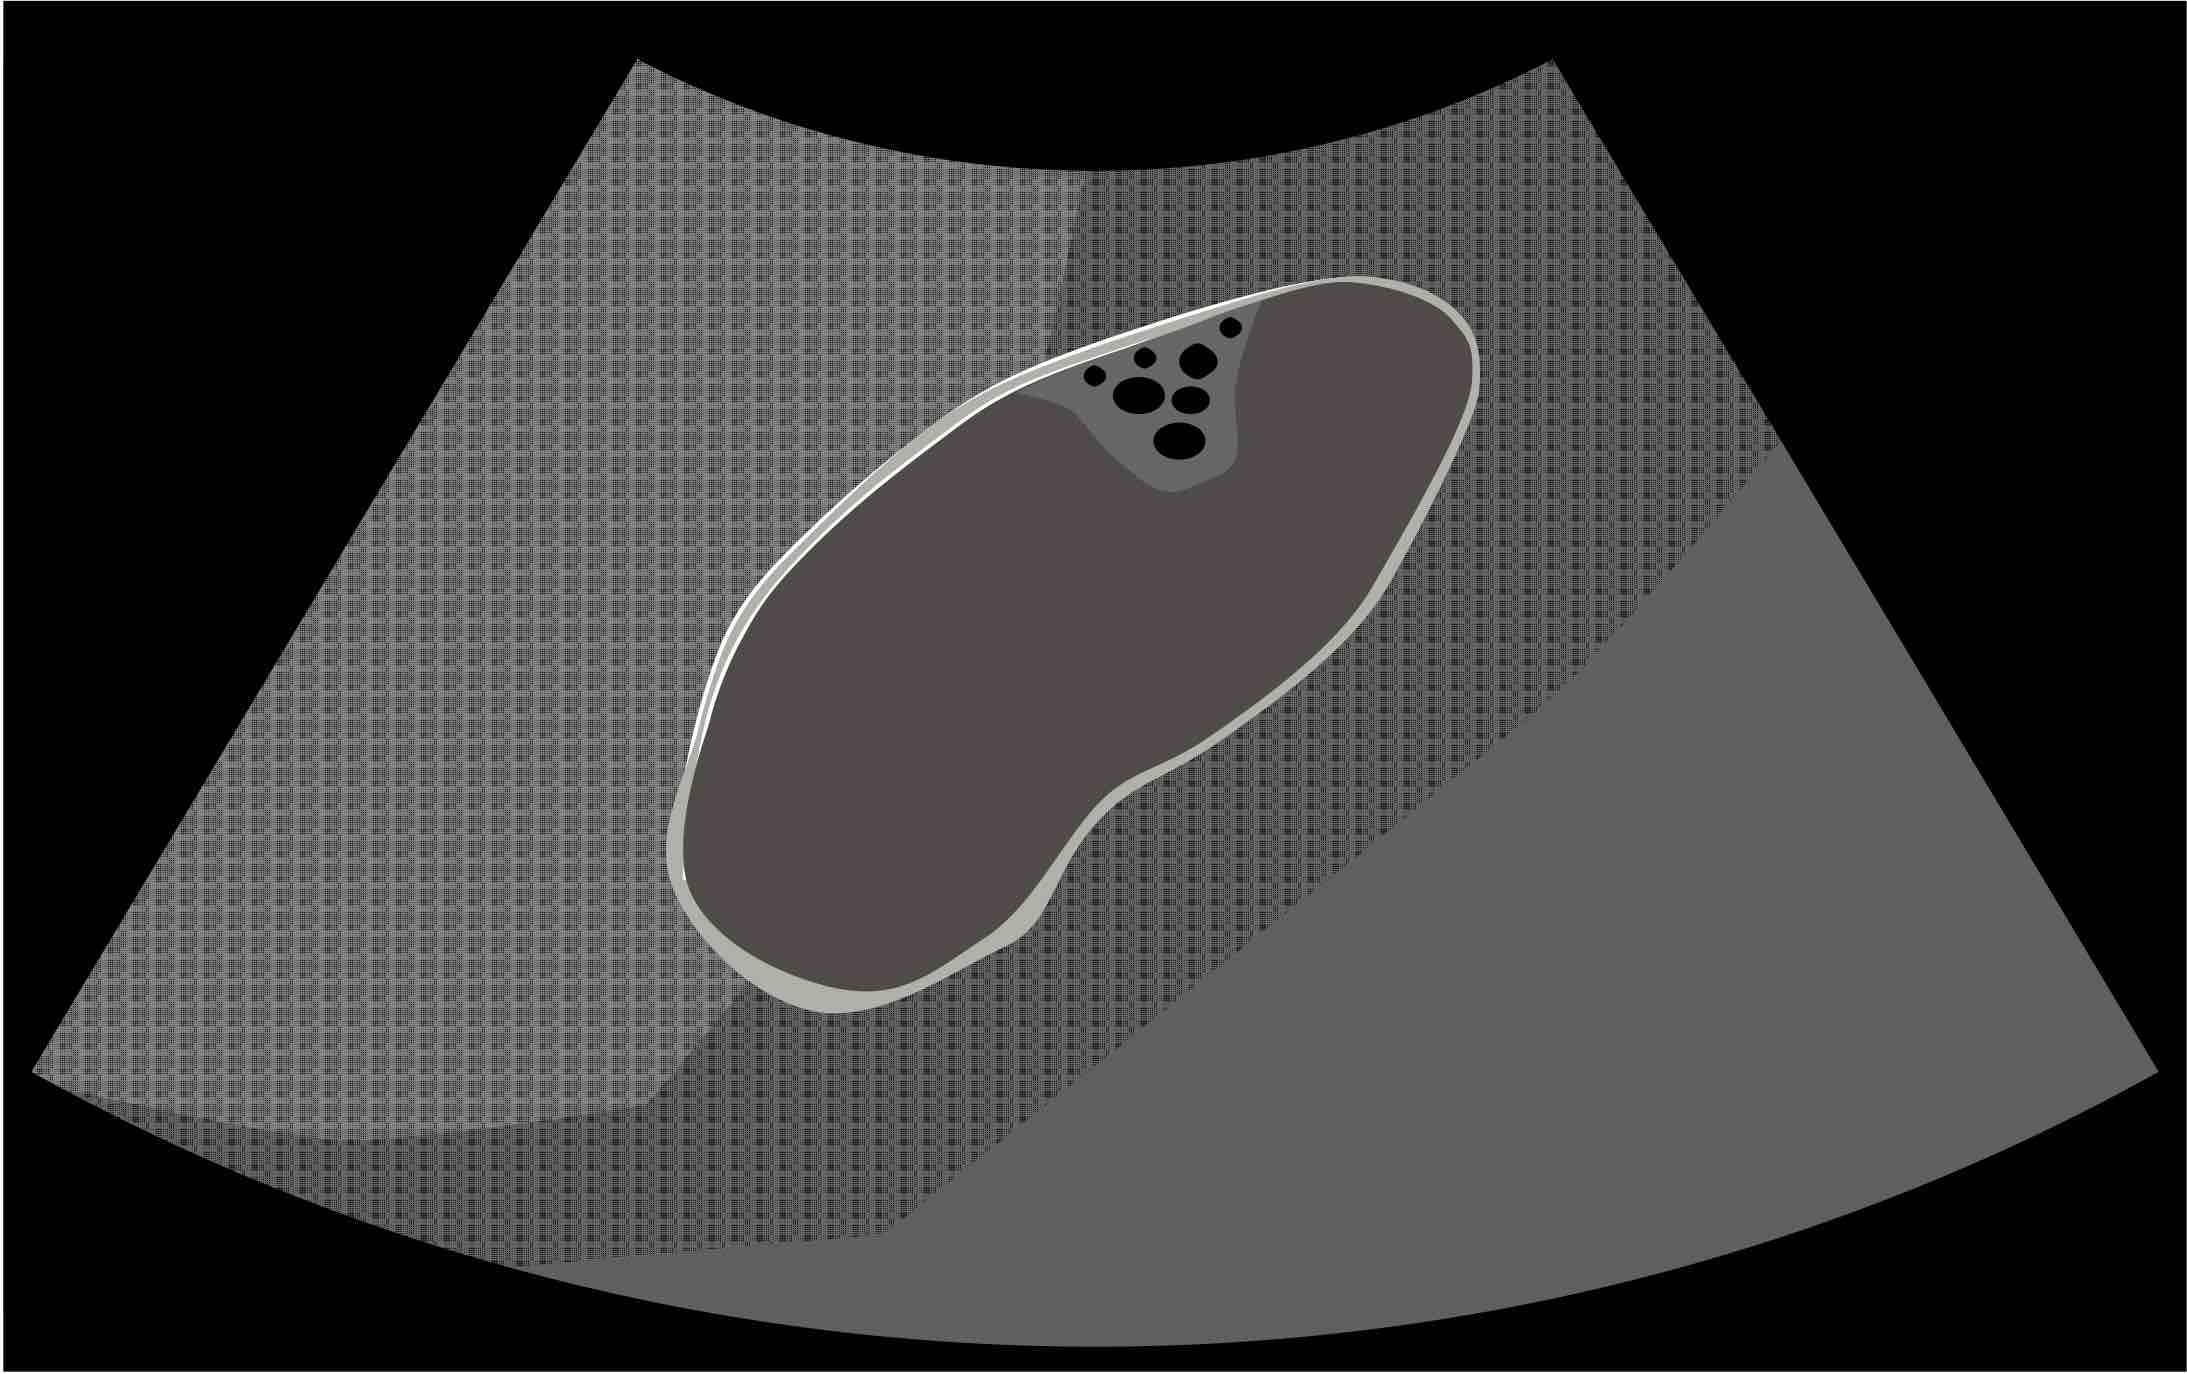

胆嚢腺筋腫症

・胆嚢壁のびまん性あるいは限局性の肥厚で限局型からびまん型まで様々なタイプがある

・胆嚢の粘膜上皮が胆嚢壁の筋肉の層にまで憩室様嵌入したRokitansky-Ashoff洞(RAS)と呼ばれるものが増生したもの

・胆嚢摘出症例の約10%に認められ頻度が高い

・壁内の小嚢胞構造やコメット様エコーを参考にして診断するが、胆嚢腫瘍と鑑別しがたい例もある